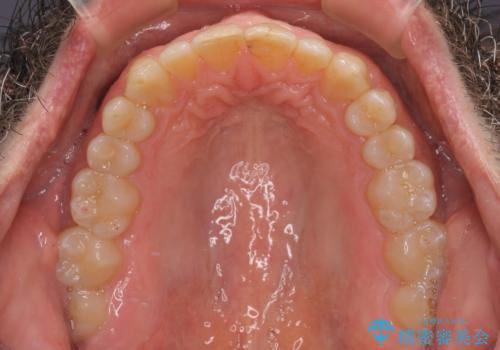

- 前歯のデコボコを気にして来院された患者様です。

インビザラインでもワイヤー装置でも対応可能でしたが、仕事の都合で来院回数を減らしたいとのことでインビザラインによる矯正治療を選択されました。

著しく咬合力が強いため、奥歯がしっかりと噛めずに治療が長引くことが懸念されました。

1セット目のインビザラインを使用した際には左右ともに大臼歯が咬み合っていなかったのですが、2セット目できっちりと仕上げることができました。